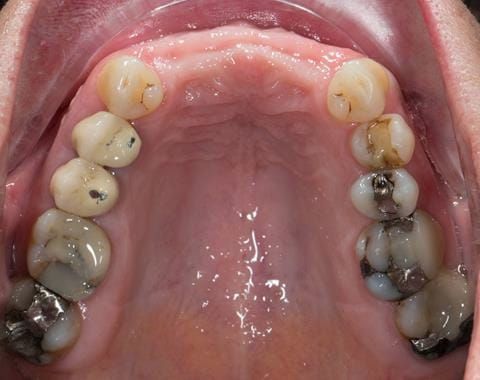

- UR2 peri-radicular periodontitis with a peri-radicular area on the root apex. Retrograde amalgam filling from a previous apicectomy. No visible root canal or root canal filling. Large circumferential marginal gap between the crown and tooth. Large post and core present. Very little tooth structure remaining resulting in a fragile tooth with increased potential for fracture.

- UR1 peri-radicular periodontitis with a small peri-radicular area on the root apex with wide blunderbuss apex. Radio-opaque root canal filling present approximately 3 mm short of the radiographic apex. Large circumferential marginal gap between the crown and tooth. Large post and core present. Very little tooth structure remaining resulting in a fragile tooth with increased potential for fracture.

- UL1 peri-radicular periodontitis with a peri-radicular area on the root apex. Retrograde amalgam filling from a previous apicectomy. Visible root canal space with no sign of root canal filling. Large circumferential marginal gap between the crown and tooth. Large post and core present. Very little tooth structure remaining resulting in a fragile tooth with increased potential for fracture.

- UL2 peri-radicular periodontitis with a peri-radicular area on the root apex. No visible root canal or root canal filling. Large circumferential marginal gap between the crown and tooth. Large post and core present. Very little tooth structure remaining resulting in a fragile tooth with increased potential for fracture.

- Other than the maxillary incisors the remaining dentition was in marginally better condition being moderately to heavily restored. Many will probably require replacement and restoration from time to time mainly from wear and tear owing to occlusal forces.